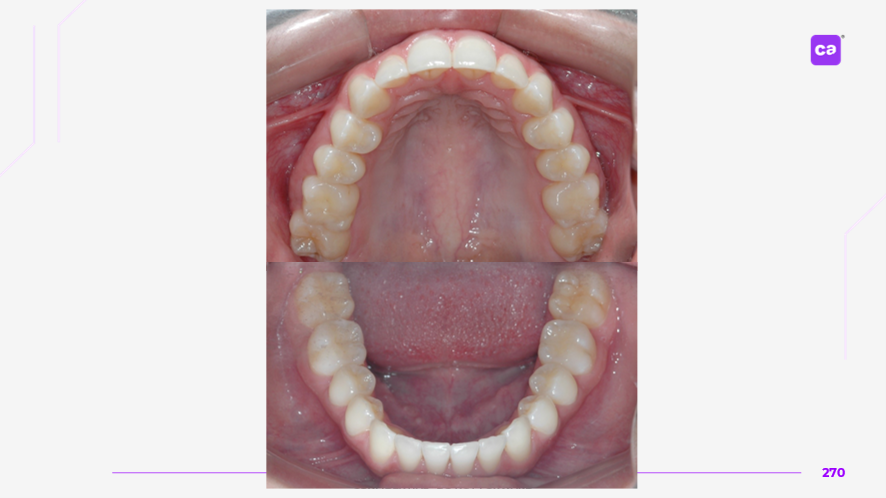

Figuras 4 – Fotos intraorais do caso clínico apresentadas em norma oclusal superior e inferior:

a) Condição inicial do caso clínico

b) Condição final do caso clínico

Na sequência apresentada, com os registros e comparação das fotos intraorais, observa-se a evolução do caso clínico desde a condição inicial até a finalização do tratamento com a conclusão do uso da série de alinhadores. Os resultados evidenciam a previsibilidade e acurácia do tratamento real em comparação às simulações e ao planejamento virtual inicial.

Observa-se a correção da sobremordida (mordida profunda), com avanço e torque vestibular dos incisivos superiores, juntamente com o nivelamento e alinhamento dentário das arcadas superior e inferior.

Além disso, nota-se o ajuste da linha média dentária superior, garantindo sua coincidência com a linha média inferior, bem como a otimização da curva e da estética do sorriso.